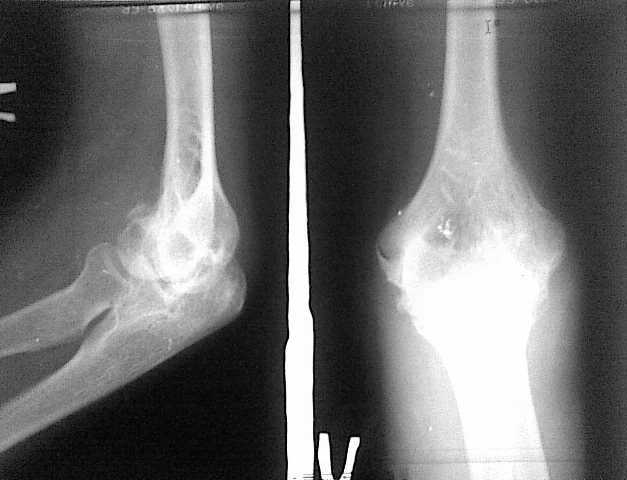

4 месяца тому назад больная 20 лет прооперирована по поводу внутри

суставного перелома наружного мыщелка плечевого сустава и локтевого

отростка локтевой кости.

Отломки фиксированы спицами, наложен гипс на 45 дней. После снятия

гипса отмечается стойкая смешанная контрактура локтевого сустава.

Проведен курс физиотерапии, рассасывающие препараты. Амплитуда

движений: сгибание 90, разгибание 110 градусов. Консервативное

лечение без эффекта.